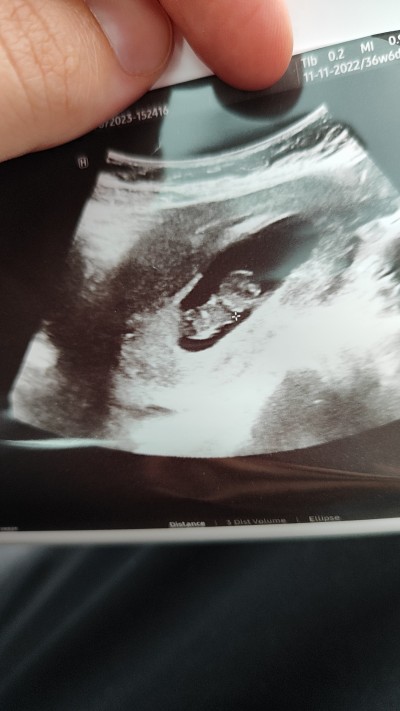

Kızlar merhaba, hiçbir önemi yok ama her anne merak ediyor cinsiyeti nedir diye, banada anlayanlar tahminde bulunabilir mi rica etsem

Gebelik haftası 9+1